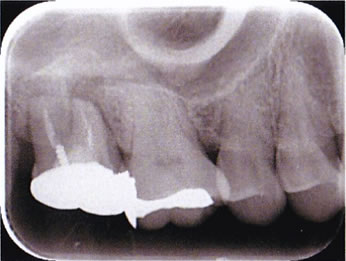

before

根管治療のレントゲン診査は2枚のレントゲン撮影(2方向)が必要です。赤丸に病変があり、根管充填が不完全です。

角度をかえることで、病巣の大きさや、根の彎曲など様々な情報が可能になります。